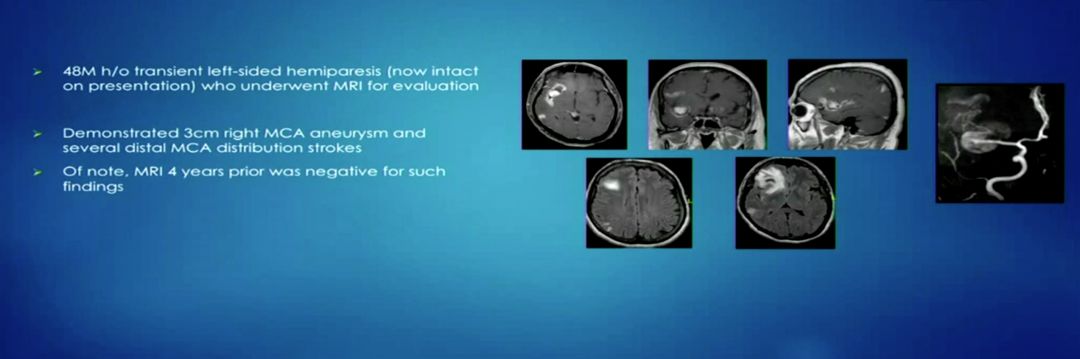

首先,UCLA罗纳德里根医学中心神经外科的Deniel Nagasawa医师汇报了一例中动脉巨大复杂动脉瘤,由于巨大的瘤体累及了M1和两支M2,同时瘤体的占位效应压迫周围脑组织导致了水肿。经过UCLA血管专业组的讨论,由于动脉瘤解剖的复杂性,如果采用介入治疗的方法,需要用支架辅助来保护两支M2,技术难度很大,同时不能消除动脉瘤的占位效应。因此对该病人采取颅内外搭桥手术,结合高流量搭桥和低流量搭桥的方式。双方对治疗方式的选择展开了热烈的讨论,也进一步讨论了术后高流量搭桥不通畅的可能因素。